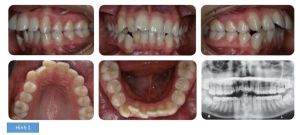

Kết quả: bệnh nhân đạt được tương quan răng loại I, độ cắn chìa giảm đáng kể và răng thẳng hàng, đều đặn, hết chen chúc. (hình 3)